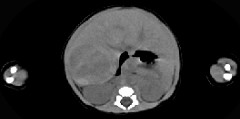

- 单项选择题男,刚刚出生5天, 上腹部膨隆,CT所见如图, 最可能的诊断为 ( )